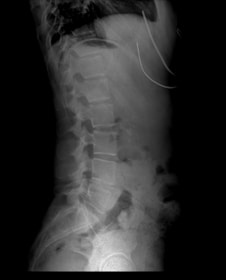

Lumbar Spondylosis

The alignment of displaced vertebrae can be achieved through medical yoga therapy.

Systematic spinal correction is possible with medical yoga therapy.